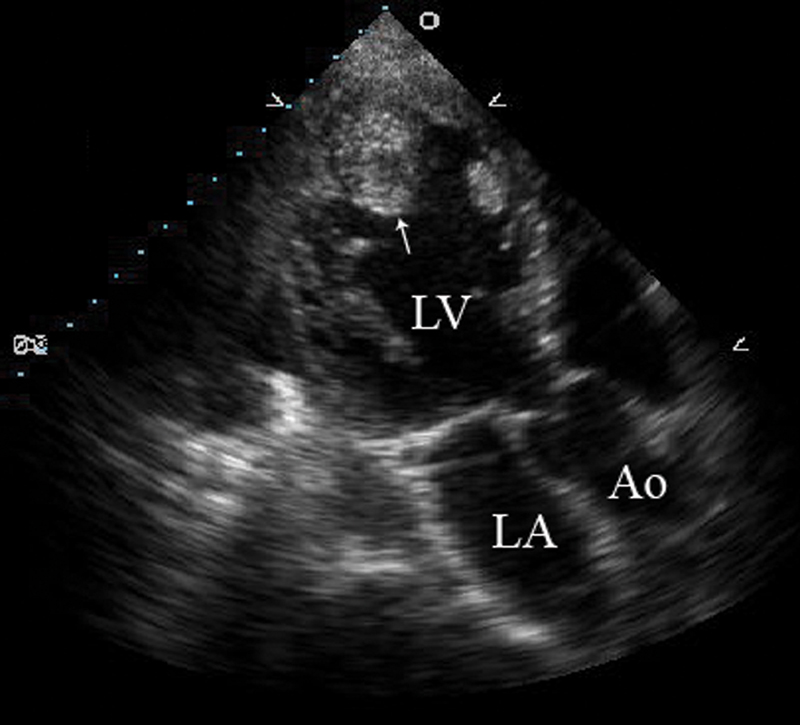

فحوصات تشخيصية لبعض امراض القلب والشرايين التاجية